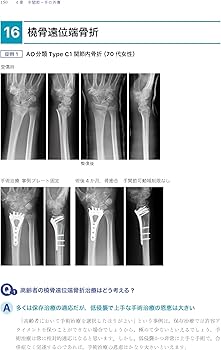

- 著者: 土田芳彦- タイトル: 考える外傷整形外科!- 出版社: 医学書院ご覧いただきありがとうございます。※本商品は裁断されておりますので、「全体的に状態が悪い」としております。※新品をそのまま裁断しているため書き込みはありません。※ ローラー痕や少々のページ折れなどあるかもしれませんが、何卒ご容赦ください。宜しくお願い致します。商品の特性上、返品交換は申し訳ございませんが致しかねますのでご理解宜しくお願い致します。| カテゴリー: | 本・雑誌・漫画>>>本>>>語学・辞書・学習参考書 |